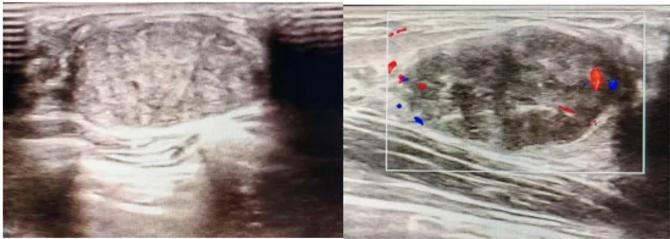

三、彩超檢查:無創(chuàng)檢查的“黃金眼”

高分辨率:可清晰顯示腫塊形態(tài)、血流信號,敏感度達80%-90%。

形態(tài):良性多呈橢圓形或分葉狀,邊界光滑。

縱橫比: 良性通常<1(橫徑>縱徑) 。

血流信號:纖維瘤血流較少,惡性常伴豐富雜亂血流。

鈣化:粗大鈣化多為良性,細小簇狀鈣化需警惕惡性。

BI-RADS分級:2-3類提示良性,4類以上需進一步檢查。

典型表現(xiàn):

橢圓形低回聲團塊,包膜完整,內部回聲均勻,后方回聲增強,周邊無“蟹足樣”浸潤。